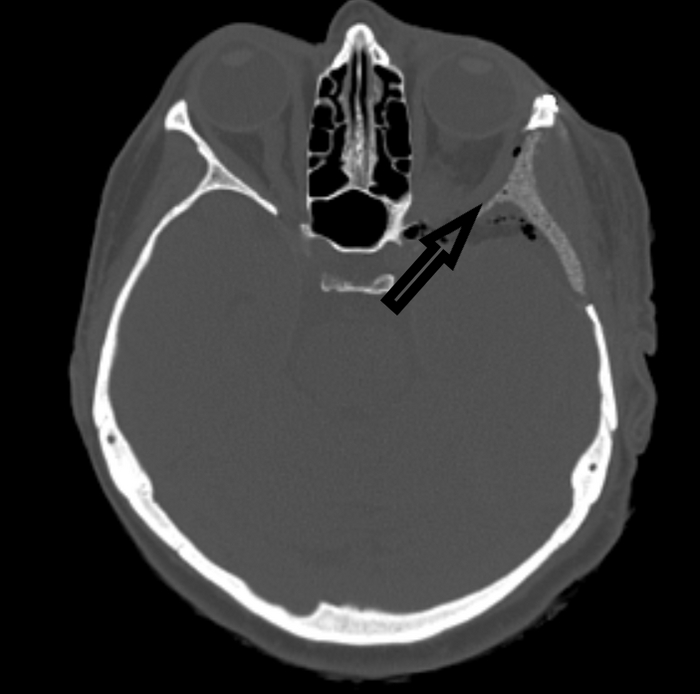

В Федеральном центре мозга и нейротехнологий ФМБА России выполнена сложная нейрохирургическая операция пациентке с гиперостатической краниоорбитальной менингиомой. Эта редкая опухоль распространяется из полости черепа в глазную орбиту. Опухоль вызывала у пациентки серьезные проблемы, в частности асимметрию лица, грубый косметический дефект и интенсивные боли в области глаза.

КТ до операции